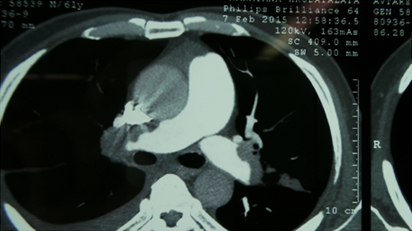

CT Pulmonary Angiography Showing Intra Pulmonary Filling defects

Filling Defects Within Pulmonary Artery